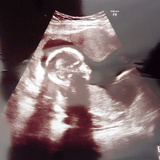

「すみません。病院がコロナ専用になるので、ここでの出産ができなくなりました」<略>定期検診に訪れた妊婦の女性(26)によると、医師から突然、切り出されたという。<略>医師からは、ほかの病院を複数紹介された。しかし、距離が遠かったり、費用が30万円ほど高くなったりするため、まだ転院先は決められていない。妊婦「急に転院迫られても…」都の3病院がコロナ専門に(朝日新聞デジタル) - Yahoo!ニュース

新型コロナウイルスの感染者数が急増した東京都は、都立と公社の計3病院を実質的な「コロナ専門病院」にすることを決めた。感染者の病床を確保するためだが、3病院では新型コロナ以外の診療や入院がほとんど停